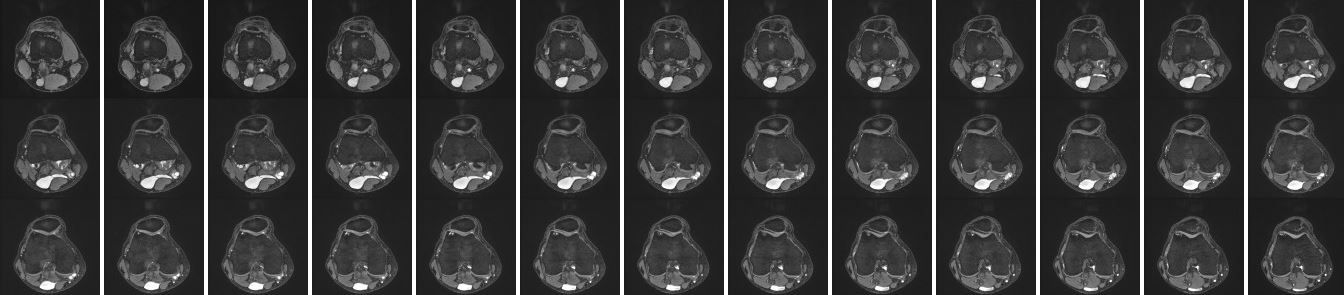

Aus dem letzten MRT...da sieht man schön, wie die Zyste irgendwo anfängt, dann relativ groß / breit / aufgefächert wird und sich dann wieder ausdünnt. Wie man das offen alles Wegschnippeln sollte, ohne viel drum herum kaputt zu machen?

Bakerzyste.JPG